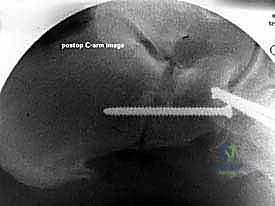

* الأشعة السينية (X-rays) مع تحمل الوزن: ضرورية لتقييم درجة انهيار القوس وزوايا العظام (مثل زاوية تالونافيكولار Meary's Angle).